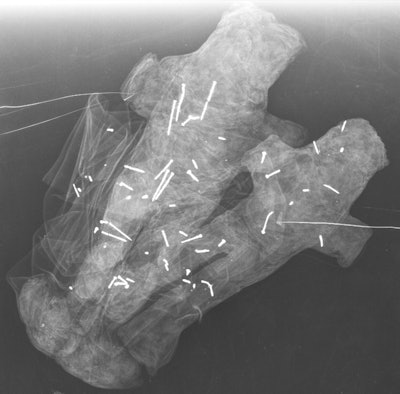

Finally, the paired dolls were not clearly identifiable as male or female, they wrote. The fact that they are a duo could signify a couple, a father and son, or siblings. The researchers found 58 needles in these two dolls: 20 in the white doll, 33 in the black doll, and five scattered across the fabric of each.